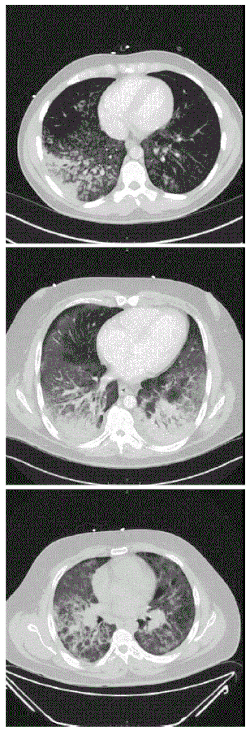

| CT scan of the chest showing diffuse lung infiltrates found in three cases of vaping-associated pulmonary injury | |

There are non-specific laboratory abnormalities that have been reported in association with the disease, including elevations in white blood cell count (with neutrophilic predominance and absence of eosinophilia), transaminases, procalcitonin, and inflammatory markers.[4][66] Infectious disease testing, including blood and sputum cultures and tests for influenza, Mycoplasma, and Legionella were all found to be negative in the majority of reported cases.[66] Imaging abnormalities are typically bilateral and are usually described as "pulmonary infiltrates or opacities" on chest X-ray and "ground-glass opacities" on chest CT.[4]